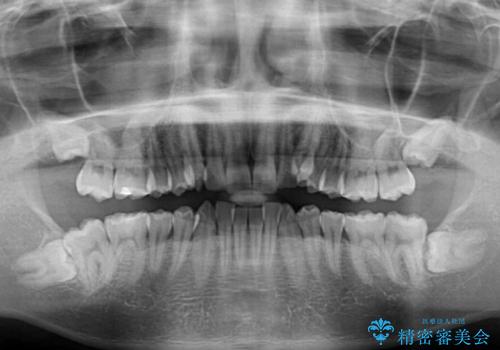

- 上顎の八重歯と前歯のデコボコを気にして来院された患者様です。

八重歯の移動量が多く、インビザライン単体での治療は困難と判断し、補助装置により八重歯移動後にインビザラインを用いることとしました。

上顎のみの抜歯矯正をインビザラインで行う場合、奥歯の前方移動がインビザラインでは苦手のため、奥歯の咬み合わせが不十分となることがあります。

今回の治療では終了時に奥歯は接触しているものの、接触の程度は物足りないものがある状態でした。今後保定期間に少しずつ奥歯の咬合を改善させていくことになります。